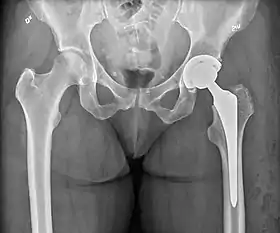

Post-operative projectional radiography is routinely performed to ensure proper configuration of hip prostheses.

X-ray of the hips, with a right-sided hemiarthroplasty